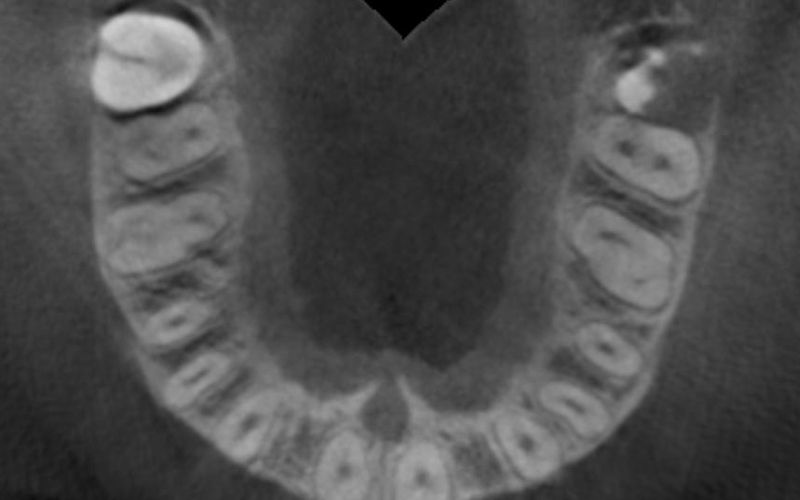

Al cabo de todo este tiempo se realizó un CBCT maxilar para iniciar la planificación de la cirugía de colocación de dos implantes en posición de 12 y 22. Durante el análisis de las imágenes radiográficas, tal y como indican las mediciones que se realizaron, se observó una limitación de espacio en sentido mesio-distal entre 11 – 13 y 21 – 23, que iba a impedir la colocación de dos implantes estándar de 3.3 mm de diámetro.

Dadas las circunstancias y para buscar una resolución óptima del caso, se decidió utilizar implantes Biomimetic Pearl de diámetro reducido de 2.8 mm de Avinent Implant System. Estos mini-implantes disponen de una línea protésica para rehabilitaciones unitarias y, dentro de su amplia gama, encontramos el que se ajustaba mejor a las exigencias del caso, permitiendo mantener perfectamente la distribución de espacio para poder respetar la biología de la rehabilitación.